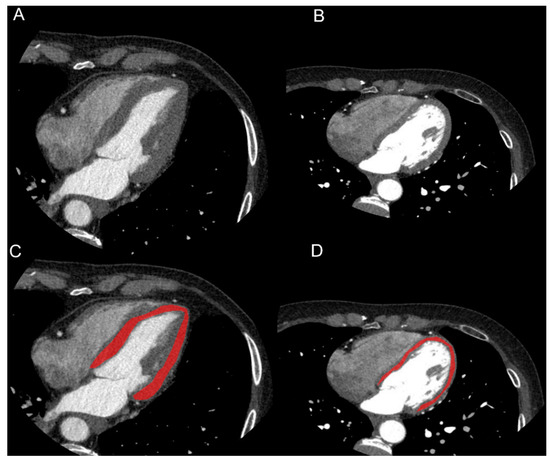

In one image per patient, on a 4-chamber view and at 75% of R-R interval, LV was segmented using a polygonal region of interest (ROI) by two radiologists in consensus. Care was taken to not include blood in LV cavity, epicardial fat, myocardial trabeculations or major coronary arteries in the ROI (Figure 1).

Figure 1.

Images and segmentation examples of cardiac CTs of patient with history of hypertension (HTN, (A–C)) and without history of hypertension (NC, (B–D)). On a 4-chamber view, LV was segmented using a polygonal region of interest (ROI). Care was taken in not including blood in LV cavity, epicardial fat or major coronary arteries. Clinical data of HTN patient were: male, 73 years old, BMI = 24.7 kg/m2, history of diabetes, dyslipidemia and hypertension, septum width: 14 mm. Clinical data of NC patient were: female, 61 years old, BMI = 18.9 kg/m2, smoker, familiarity with cardiovascular disease, no history of diabetes, dyslipidemia and hypertension, septum width: 8 mm.